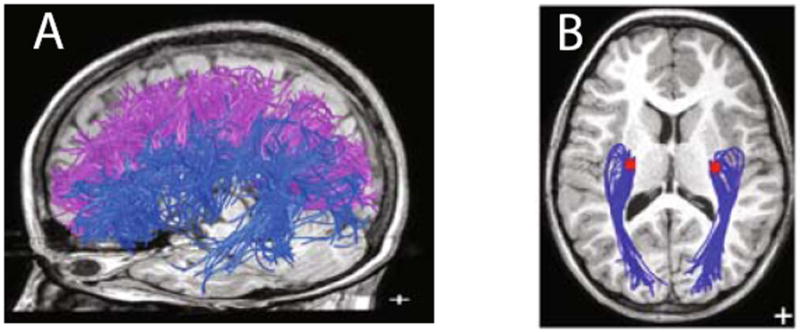

The BlueMatter human projectome contains the major intra-hemispheric white matter pathways as reported by Wakana et al. [14]. The projectome also contains fasciculi not present in the atlas a) fascicles that connect the corpus callosum to lateral cortex (Figure 3A, blue) and b) optic radiation (Figure 3B). These tracts are rarely found using local, greedy methods.

Fig. 3.

Important fiber tracts within the BlueMatter projectome. (A) Pathways project from corpus callosum to lateral surface (blue). (B) Optic radiation (blue) connecting lateral geniculate nucleus (red) to primary visual cortex.